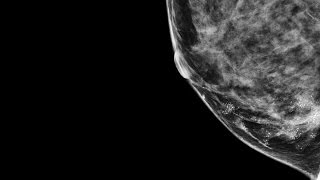

Breast Density - Stanford Health Care (SHC) - Stanford ...

Doctors to spot cancer on mammograms. Dense tissue appears white on a mammogram. Lumps, both benign and cancerous, also appear white. So, mammograms can be less accurate in women with dense breasts. Breast Density Stanford Breast Imaging ... Fetch Doc